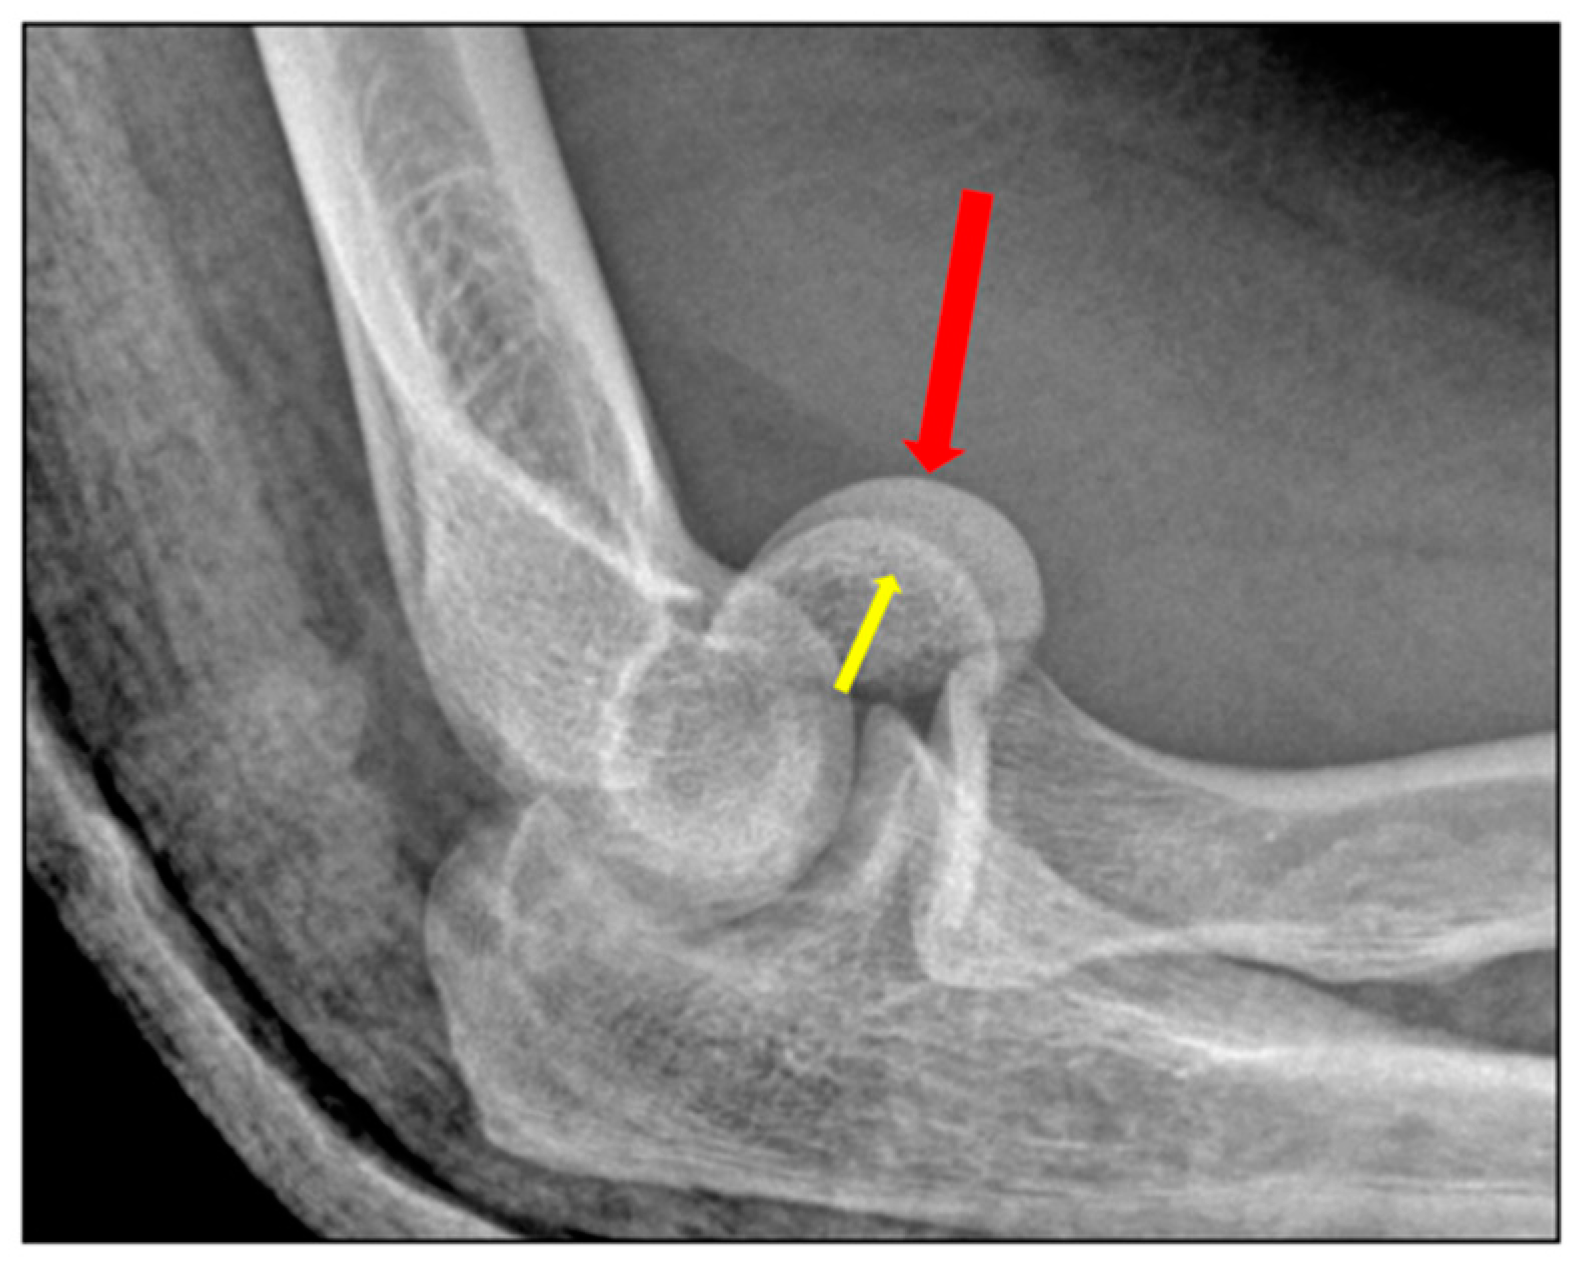

3. Imaging